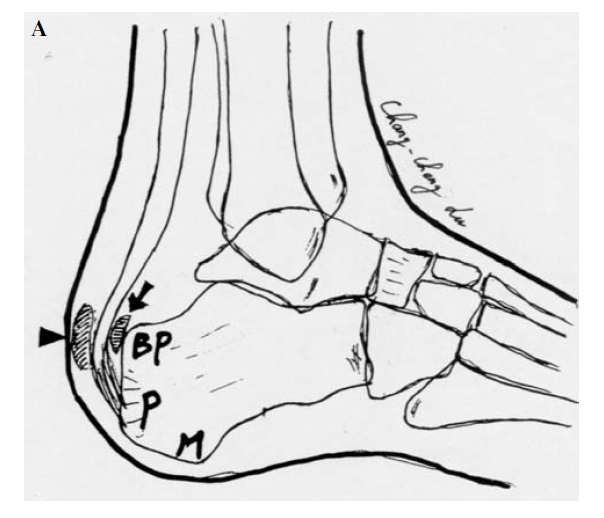

X:Fowler and Philips angle,44°-69°

CLA角:Chauveaux-Liet  Angle,CLA=α-β,>12°怀疑,X/Y值:<2.5高度怀疑

FPA和PPL不可靠,Haglund综合征与跟腱钙化和跟骨后方骨刺关系密切。

Zadek于1939年最先提出,跟骨楔形闭合截骨治疗Haglund综合征。

X/Y由小于2.5到大于2.5